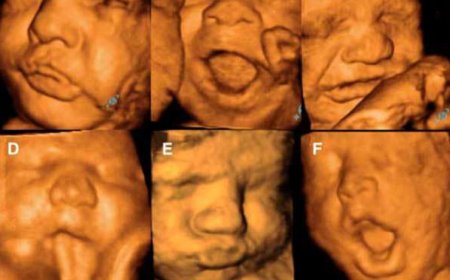

Bebekler Ağlamayı Doğmadan Önce mi Öğrenir?